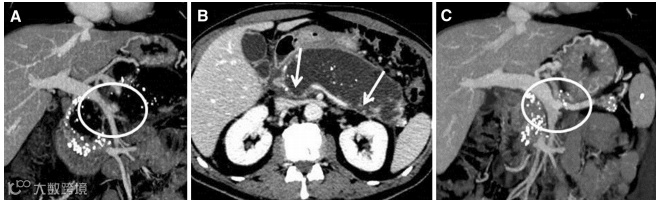

(图源自文献)

A,一例57岁男性患者,冠状位CT显示:慢性胰腺炎的坏死组织中可见部分门静脉和完全脾静脉血栓形成(圆圈)。

B,轴位CT提示:脾静脉部分血栓形成(箭头),这与坏死的胰腺组织大量积聚有关。

C,抗凝治疗后6个月的冠状位CT提示:脾静脉和门静脉完全重新再通,坏死组织积聚消失(圆圈)。